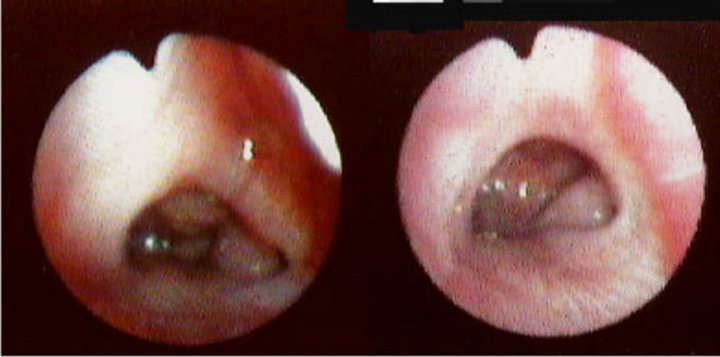

Bác sĩ có thể hỏi và sau đó kiểm tra tai, mũi, họng của trẻ và sờ cổ dọc theo hàm. Để có được cái nhìn thực sự gần gũi, bác sĩ có thể yêu cầu chụp X-quang hoặc nhìn vào đường mũi bằng kính chuyên khoa.